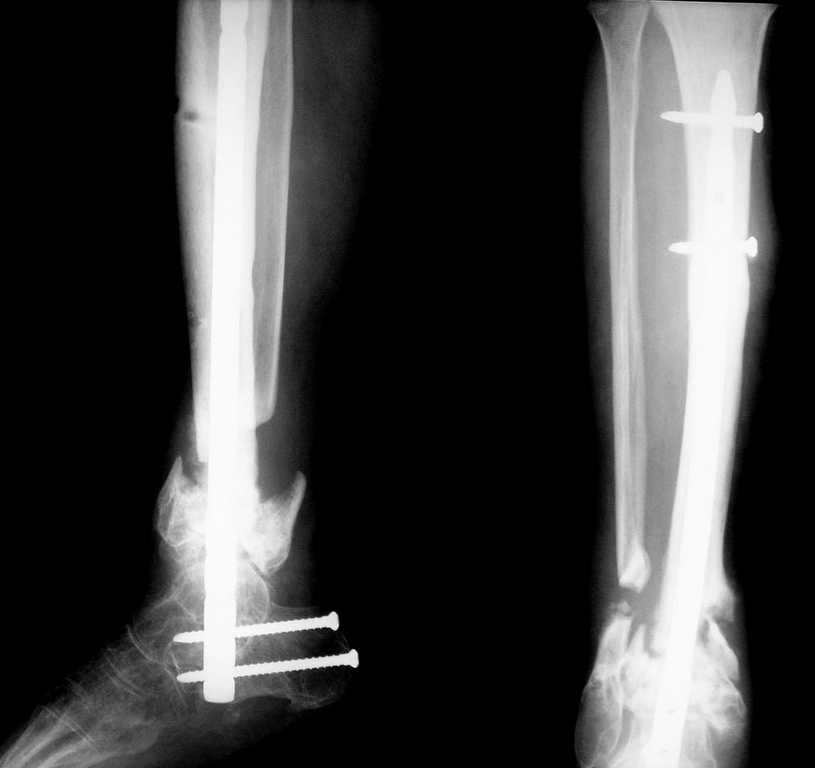

Здравствуйте коллеги! К нам поступил пациент 52 лет. Травму получил два года назад,открытый перелом н/3 костей голени.

Со слов больного год лечили аппаратом, винты ввели при ПХО, потом ещё год ходил в гипсовой повязке.Сейчас ложный сустав в н/3, патологическая подвижность при попытке опоры.Наш вариант лечения: резекционная остеотомия малоберцовой, удалить винты,остеосинтез стержнем с рассверливанием и блокированием через пятку, естесственно с артродезом.Кожа чистая, хотя и в рубцах. Или опять аппарат?

Вот что в итоге получилось. Вопрос по поводу нагрузки: может сразу дать? и зря я поставил статический винт?

DFN "остеомед",под правую ногу взяли левый гвоздь,с учётом нормального вальгирования пяточной кости. Хотел поставить HAN со спиральным лезвием,специально созданный для этого, но из-за организационно-технических моментов не удалось. Ну да в следующий раз....

Алексей, а в каком положениии стопы получилась фиксация? Не в эквинусе ли стопа??

Движений в голеностопном суставе совсем не было, устранить эквинусную установку можно было только за счет угла открытого кпереди в зоне ложного сустава. Поэтому выбирая между восстановлением оси конечности и эквинусом я выбрал ось.Возможно эквинус компенсирует укорочение 2,5 см (которое при динамизации увеличится). Наверно не так уж и страшно, если больной теперь обречён на обувь с каблуком?